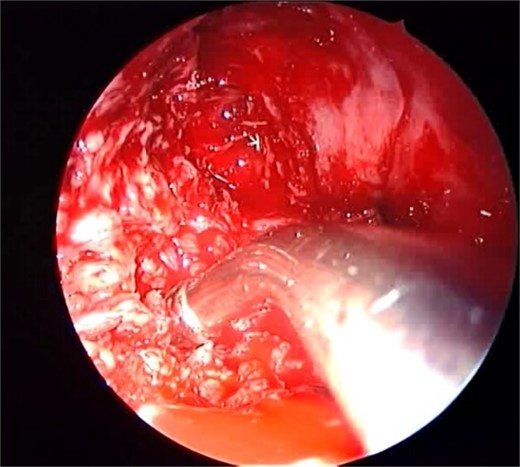

Isolated maxillary acute fulminant invasive fungal sinusitis

A 12-year-old young girl with relapsing acute myeloid leukemia presented with fever, headache, and left maxillary facial pain. Her symptoms were associated with blood-tinged nasal discharge. Nasal endoscopic examination showed friable ulcerative mucosa of the left middle turbinate and osteo-meatal complex which raised a clinical suspicion of invasive fungal sinusitis. Thus, a contrast-enhanced CT scan (CECT) (Fig. 3) was necessary which showed enhancing left maxillary sinus opacity suggestive of acute invasive fungal sinusitis. The patient underwent urgent endoscopic medial maxillectomy with removal of invasive fungal debris (Fig. 4) along with debridement of left middle turbinate, medial maxillary wall, and orbital floor. A diagnosis of invasive mucormycosis was confirmed by histopathology. The patient was started on aggressive treatment in the form of intravenous and oral antifungal medications. She was regularly followed up for the next 5 years with no evidence of recurrence.

Intra-operative endoscopic maxillary examination (A and B) showing invasive fungal debris.